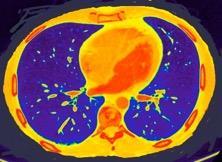

Derrame pleural..33,3% Derrame bilateral.26,7% Ganglios mediastínicos e hiliares..66,7%..

No hiliares

Okada F et al. Chest HRCT findings in acute transformation of adult T-cell lymphoma/leukemia. Eur Radiol 2015

Vidrio deslustrado 60%. Consolidación 33,3% Nódulos…33,3%